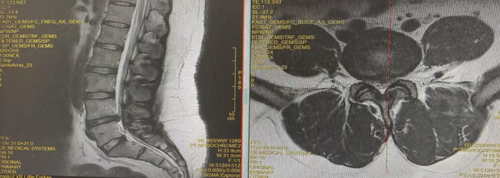

28岁的男性患者,体重达110kg,腰腿痛半年余,长期在外务工,在当地行针灸、理疗及口服消肿止痛药物效果不佳,症状反复并逐渐加重,严重影响日常生活,近日劳累后再次出现腰部疼痛并右下肢疼痛与麻木无法长距离行走,回家乡到奉节县中医院就诊。经检查诊断为腰椎间盘突出症并神经根病。

骨伤科陈治太副主任医师团队充分评估患者相关情况后,考虑患者年轻、症状重,椎间盘组织含水量高、弹性好,建议为唐先生利用微创手术彻底解除病痛。经过充分的术前评估讨论,陈治太医生团队为患者实施AUSS技术下髓核摘除和纤维环缝合修复术,手术顺利,唐先生术后右下肢疼痛症状完全消失,术后第六天康复出院,患者及家属对手术效果非常满意。